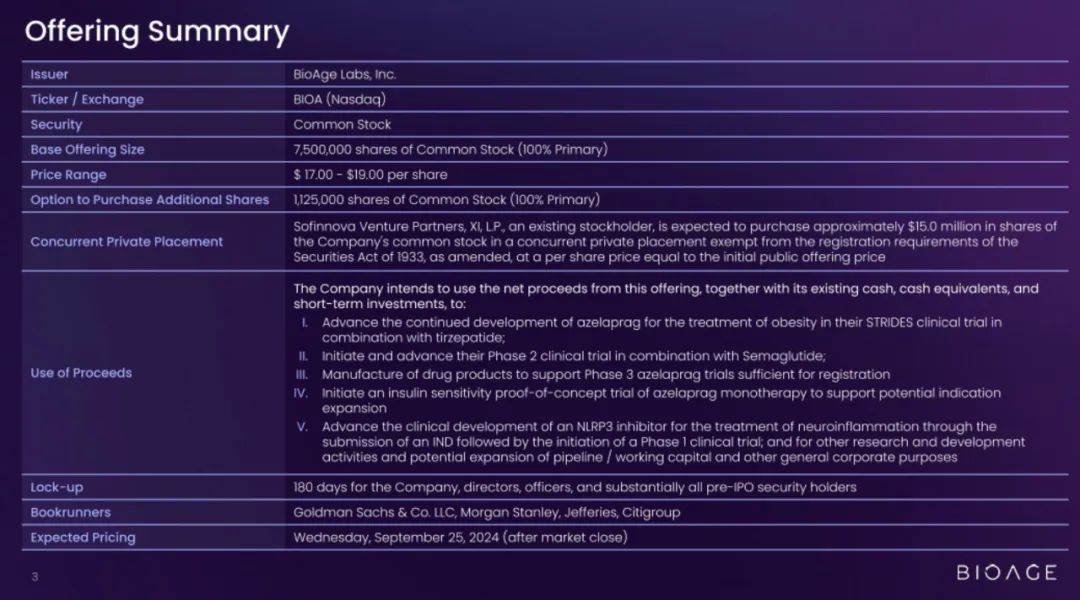

生物科技初创公司BioAge Labs(股票代码为:“BIOA”)日前更新招股书,准备2024年9月底在美国纳斯达克上市。

BioAge Labs发行区间为17美元到19美元,发行750万股,最高募资1.43亿美元。

BioAge Labs正在进行的 STRIDES 临床试验将评估阿泽拉普拉格与礼来公司 (Lilly) 以 Zepbound® 为商品名销售的替泽帕肽联合使用的效果,预计在 2025 年第三季度公布顶线结果。第二项 2 期临床试验将评估阿泽拉普拉格与诺和诺德以 Wegovy® 为商品名销售的索马鲁肽联合使用的效果,预计在 2025 年上半年启动。

BioAge Labs还计划在 2025 年上半年启动一项针对阿泽拉普拉格单药治疗的胰岛素敏感性概念验证试验,以支持潜在的适应症扩展。我们还在开发口服小分子脑渗透性 NLRP3 抑制剂,用于治疗由神经炎症引起的疾病。

BioAge Labs预计将在 2025 年下半年提交 NLRP3 抑制剂的新药临床试验申请 (IND),如果获得批准,将于2026年上半年启动1期临床试验。

BioAge Labs迄今为止,已经募资超过3亿美元,投资方包括Andreessen Horowitz、Pear Ventures以及AME Cloud Ventures等。

其中,2024年2月,BioAge Labs刚宣布完成1.7亿美元的D系列轮融资,以加速肥胖和代谢疾病治疗的开发。